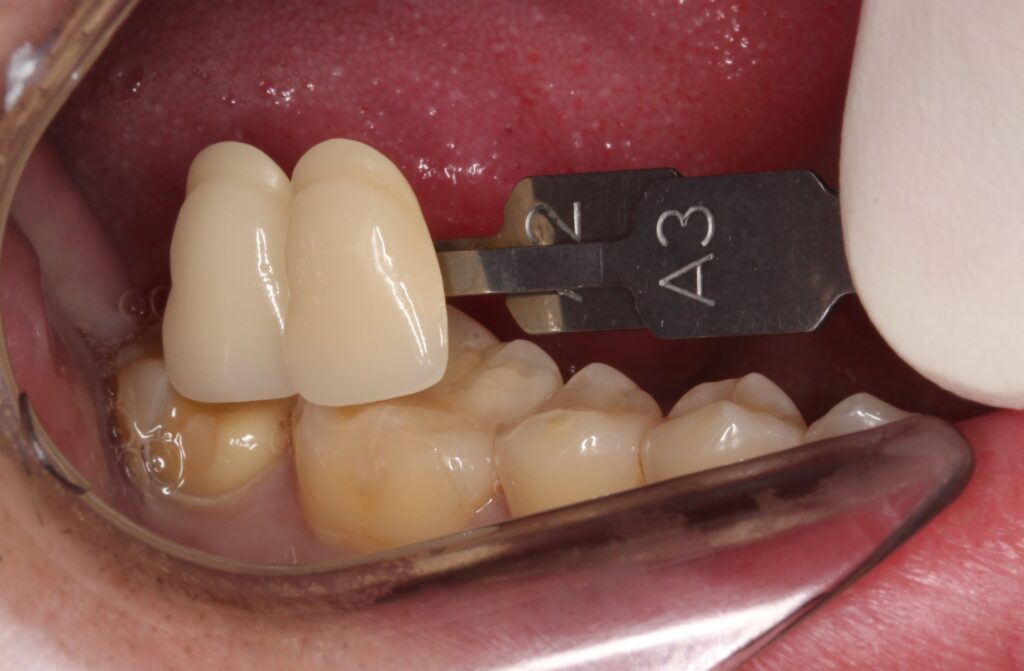

後は、形を整えて型取りをしていきます。今回はセラミックインレーにて修復を行います。

歯の色を色見本でチェックして、専門の歯科技工士が、その方に合ったセラミックを製作します。